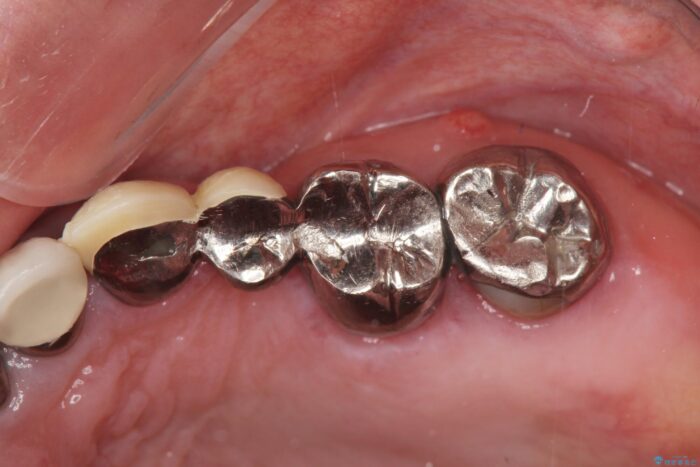

長い間気にしていた、笑ったときに見える銀歯を白くしたいとご来院されました。

まず検査を行い、歯周病や歯内の問題がないことを確認しました。

銀歯をジルコニアセラミックへと換えることで、審美性・清掃性の高い仕上がりを目指します。